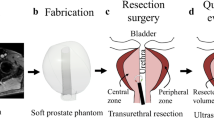

CT (computer tomography) images of ten human patients (44–72 y) with filled bladders were obtained from the University Medical Centre Mannheim, approved by the Ethical Committee II, University of Heidelberg, Germany, under the reference number: 2015-549 N-MA. As illustrated in Fig. 1, the CT images were extracted with an open-source medical image viewer (Horos™, horosproject.org, Purview, Annapolis, MD, USA), reconstructed, and exported as.stl files. The most representative bladder form was selected according to the medical experts and the model was scaled to 150 mL in volume at a relaxed state. Anatomical details, including the urethra, the interureteric bar, and the blood vessels, were designed based on cystoscopic videos in consultation with medical experts and added onto the surface of the model, using computer-aided design (CAD) software (Solidworks 2019, Dassault Systèmes Corp., Waltham, MA, USA). Three molds were designed: (1) an inner mold that matches the relaxed volume and the shape of the bladder and includes important anatomical structures, such as interureteric bar, and the vascular network; (2) an outer mold to define the thickness of the bladder wall; and (3) a urethra mold to define the shape and thickness of the urethra. In total, three different negative bladder molds (inner mold, an outer mold, and a urethra mold) were designed, as shown in Fig. 2. FlexBlad’s wall was prepared by a molding process. The outer molds being prepared in three different wall thicknesses, i.e., 2 mm, 3 mm, and 5 mm, allowed FlexBlad to have respective compliance.

Fabrication of FlexBlad

The negative molds were printed with VeroClear® material in a 3D printer (Object 260 Connex, Stratasys, Israel). In order to realize its high flexibility, a soft silicone material (Ecoflex 00-20, Smooth-on, Macungie, PA, USA) was chosen to fabricate the phantom. First, a mold release agent was evenly sprayed on all surfaces of the molds and dried in a fume hood for 30 min. The silicone material was prepared by thoroughly mixing Part A and B in 1:1 of the weight ratio. For coloring, the mixture, 1 wt% of coloring agent (red color for the blood vessels and skin color for the bladder wall and the urethra) was added. The mixture was vigorously stirred mechanically and degassed in a vacuum chamber for 10 min to remove the air bubbles. As shown in Fig. 2, a negative pattern of the blood vessel network on the inner mold was filled with red-colored silicone material, and the viscous material was held in place due to the surface tension in the negative pattern, and the material was solidified using a heat gun at 150 °C. Subsequently, the blood vessel mold was assembled with the outer mold, and a rectangular junction on the inner mold fits with a slot on the outer mold (Fig. 2d) to ensure a precise assembly without any rotation or translation. The same silicone material (skin-colored) was filled between the molds and cured at 65 °C, and the two layers of silicone material firmly adheres to each other. The bladder phantom was released from both molds mechanically. The urethra that was prepared by similar molding steps was assembled to the bladder neck by applying the same silicone material used for the bladder wall and then the silicone material was thermally cured with a heat gun. The tumors (~ 350 – 700 mm3 in volume) were fabricated using the same material in different colors, embedded with a magnet (NdFeB, 4 × 4 × 4 mm3, Supermagnete, Germany) to allow the repositioning with the control of an external magnet. Biopsy simulation was performed using biopsy forceps (5 Fr., 73 cm, KARL STORZ GmbH, Tuttlingen, Germany).

The bladder phantom with detailed vascular structures were realized by the multiple molding process on 3D-printed molds (Fig. 2). 3D printing offered a spatial resolution to achieve sub-millimeter complicated structures that are designed in the digital bladder model. The designed blood vessel network was engraved on the outer surface of the inner mold (Fig. 2a). By filling viscous silicone material in the narrow negative-patterned network, the material remained in the gap until curing. Then, the outer mold was assembled and covered the inner mold to unify to the phantom bladder wall. The step-wise assembled parts were well-integrated and no delamination was observed under large strain (> 200%). This fabrication method replicates the vascular network down to 0.5 mm width with complicated 3D geometries, mimicking the human bladder vascular network. Various endoscopic explorations of the phantom led to a continuous improvement of the artificial bladder tissue towards the final results (Fig. 4, Supplementary Video S1).